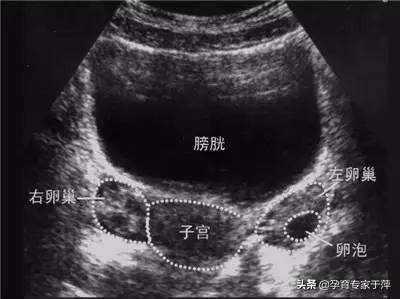

B超:

对卵巢、子宫等情况而进行检查,测量子宫大小、内膜厚度、卵巢大小、卵泡个数、直径,以及是否有生殖系统疾病(如子宫肌瘤、子宫内膜息肉、子宫畸形、卵巢肿物等)。